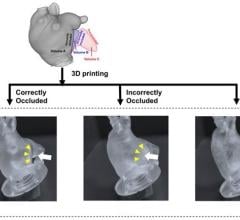

WhiteClouds’ patent pending "Hinge and Slice" proprietary designed models are used in complex surgeries across the nation, providing granular, detailed patient-specific models. Jay Bishoff, M.D., urologic surgeon and director of the Intermountain Urological Institute for Intermountain Healthcare, stated, “Having performed over a thousand procedures, I am confident that 3-D models can play a role in helping good surgeons become great. “

WhiteClouds also announced the launch of 3DyourSCAN, a life-size color printed, anatomical model of a patient's computed tomography (CT) or magnetic resonance imaging (MRI) scan designed to improve collaboration and education between physicians and patients.